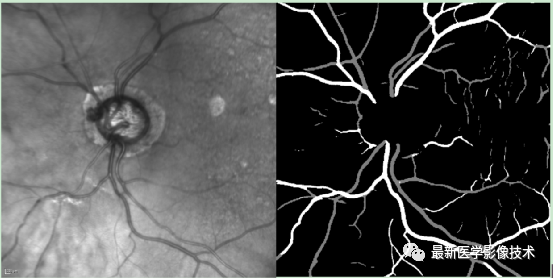

4、验证集分割结果,左图是眼底图像,中间是金标准图像,右图是分割图像

5、测试集部分分割结果